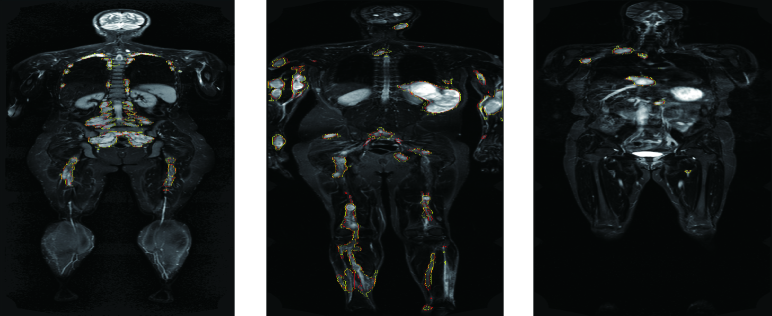

Fig. 1 depicts two NF1 cases of WBMRI with the ground truth segmentation of tumor regions contoured in yellow. Accurate detection and evaluation of tumor burden on WBMRI are important for longitudinal tracking of tumor size, which enables accurate assessment of tumor growth and treatment response. However, the detection and segmentation of neurofibroma on WBMRI, particularly PNFs, is associated with three technical challenges.

A few interactive and semi-automated segmentation methods have been developed for NF1 in the literature. Solomon et al. [16] developed an interactive 2D segmentation method for PNF that detects tumor regions within a manually defined area on each slice using a histogram-based threshold. This method failed if the histogram is unimodal or close to unimodal. Thus, manual contouring was frequently required to correct the resulting contours. Following this idea, Weizman et al. [1] proposed 15 histogram templates of various distributions from bimodal to unimodal to identify the optimal threshold. Cai et al. [3] developed the 3DQI system for semi-automated neurofibroma segmentation performed by the dynamic-threshold level set method starting from a seed region. These existing methods required a large amount of time and effort of interaction from users, either slice-by-slice or tumor-by-tumor with user-provided scribbles or initial seeds. However, as shown in Fig. 1, there might be dozens or hundreds of tumors in a single study, which put a heavy burden of interaction on users. Some work [17, 18] introduced neural networks into the segmentation of neurofibromas. Wu et al. [17] integrated CNNs into the Active Contour Model for predicting the parametric maps, while Ho et al. [18] compared a multi-spectral neural network classifier with manual segmentation on diffusion-weighted imaging data. However, these methods still relied on conventional segmentation methods, and state-of-the-art deep CNNs were not explored for neurofibroma segmentation yet. Therefore, a highly accurate and efficient neurofibroma segmentation method remained a technical challenge.